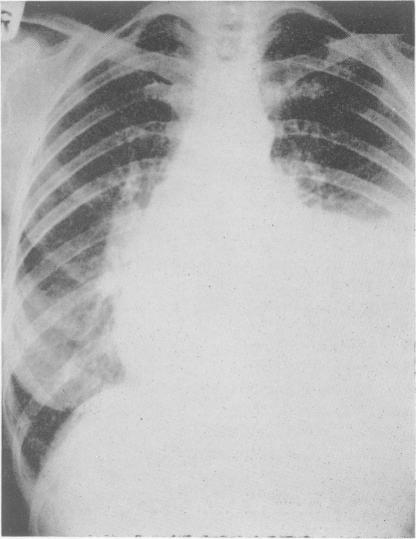

Radiology in the investigation and management of hypertension.

Postgrad Med J. 1958 Oct;34(396):514-23 passim. doi: 10.1136/pgmj.34.396.514.